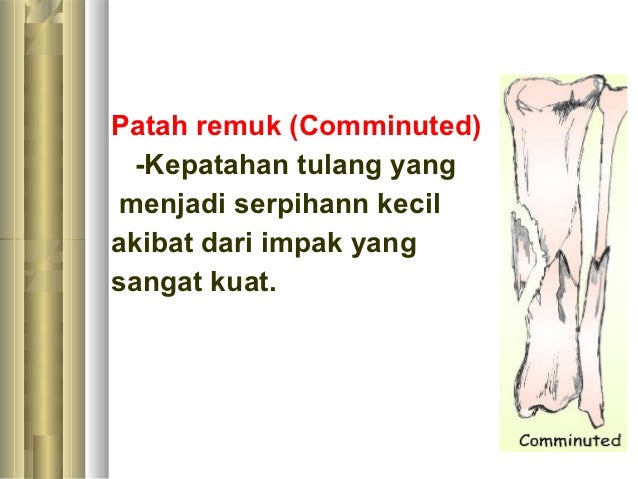

Jenis Dan Kategori Tulang Patah

Jenis Dan Kategori Tulang Patah

Fraktur - Jenis û Penyebab dan Pengobatan - IDN Medis

Fraktur - Jenis û Penyebab dan Pengobatan - IDN Medis

Bab 5 luka & patah